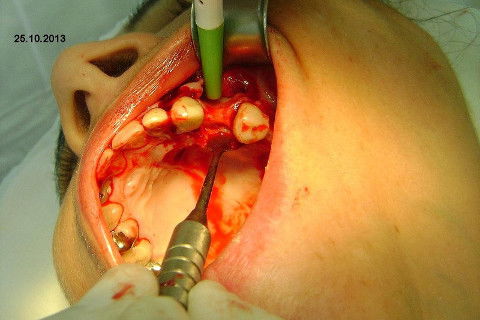

Ao exame clínico já percebemos atrofia no rebordo, uma depressão na vestibular, indicação para enxerto ósseo e dente 27 com indicação para remoção. O plano de tratamento consistiu em levantamento de seio maxilar deste lado para possibilitar instalação de implante na região do 26 (não existe dente antagônico para oclusão com o 27), enxerto ósseo na vestibular do dente 24, aproveitamento do 22,23,25, em situação satisfatória, com indicação de confecção de novas coroas.

A minha intenção era levantamento de seio e enxerto na vestibular do 24 em única sessão, mas a pedido da paciente, resolveremos o caso por etapas, consideramos a prioridade da resolução desta região dos pré molares e fizemos esta cirurgia de hoje, usando osso autógeno coletado da região da tuberosidade e próximo do alvéolo do 27. Usamos também osso bovino liofilizado Bonefill (Bionnovation) granulação média, e tela de titânio Surgitime (Bionnovation). Não foi possível a instalação do implante em conjunto com o enxerto por considerarmos rebordo extremamente atrófico na espessura (menos de 2 mm na crista e menos de 3 mm até acima do terço médio).

Agradeço aos amigos Jorge Marcos Fernandes e Heddie Ricci por nos proporcionar esta possibilidade de experimentar um material muito bom, tenho usado o Bonefill há bastante tempo com ótimos resultados e agora experimentei a tela de titânio, gostei muito, uma maleabilidade na medida certa, facilidade para cortar e adequar o formato para proporcionar um arcabouço favorável para o enxerto.